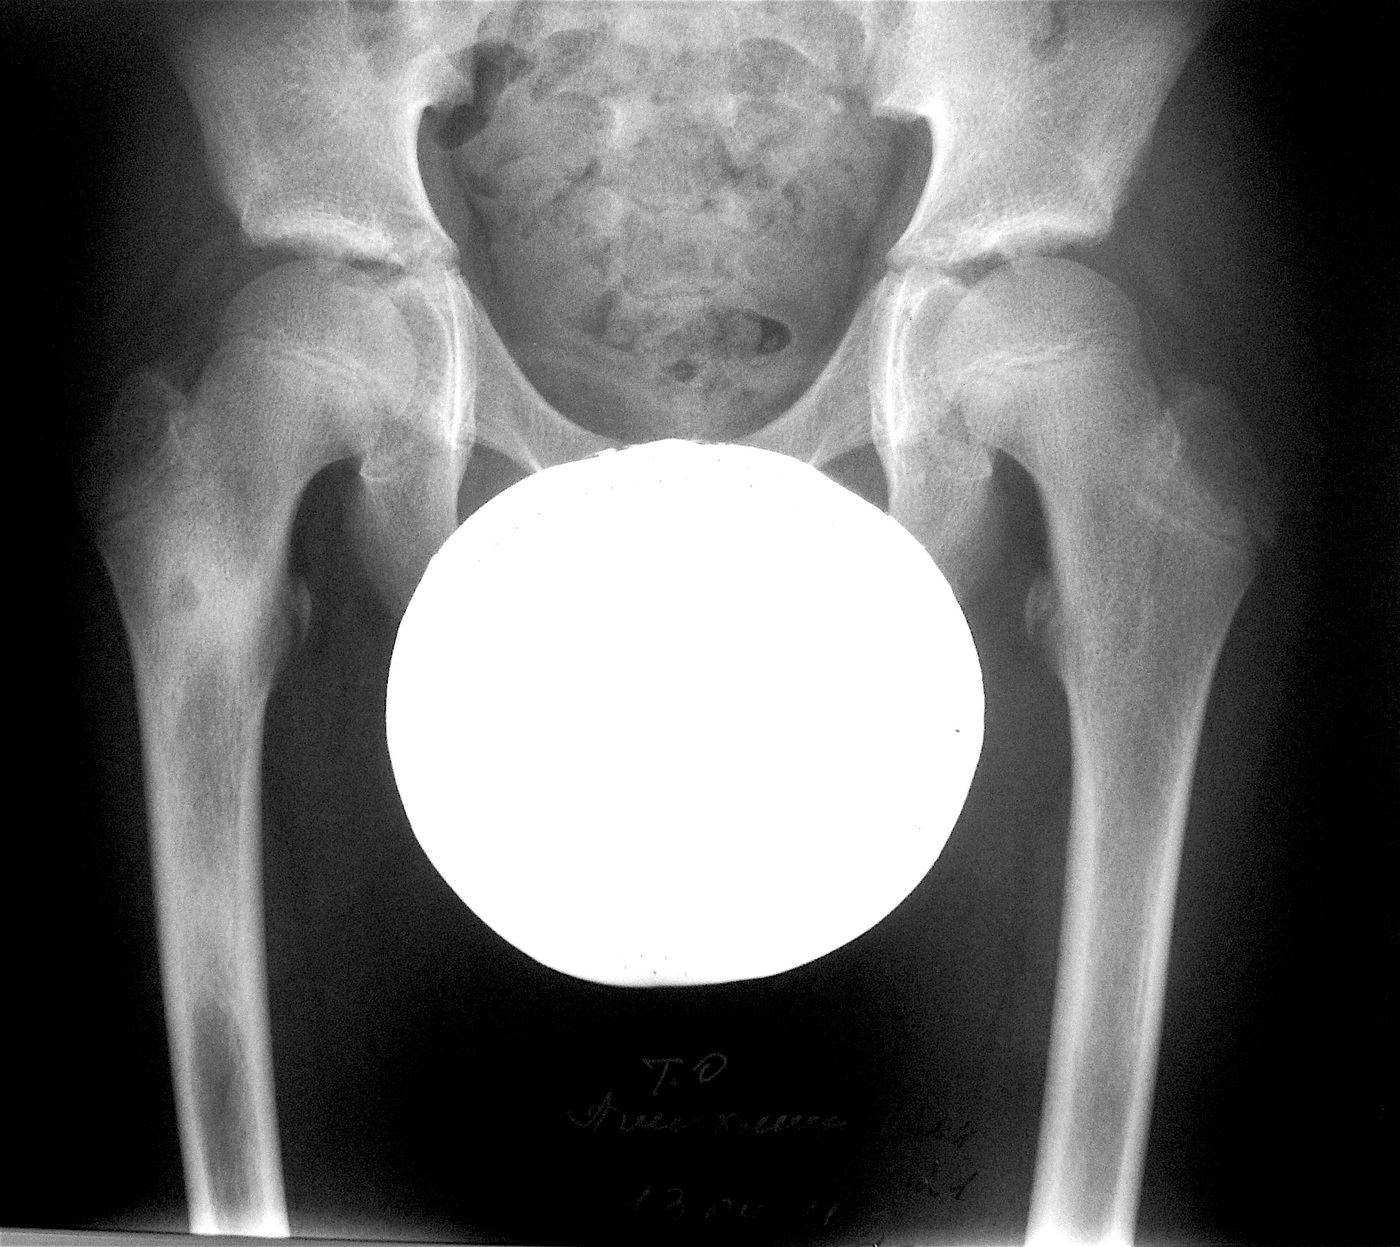

Остеоид-остеома проксимального метафиза правой бедренной кости.

Выполнена: внутрикостная резекция патологического очага, аллопластика материалом «Лиопласт».